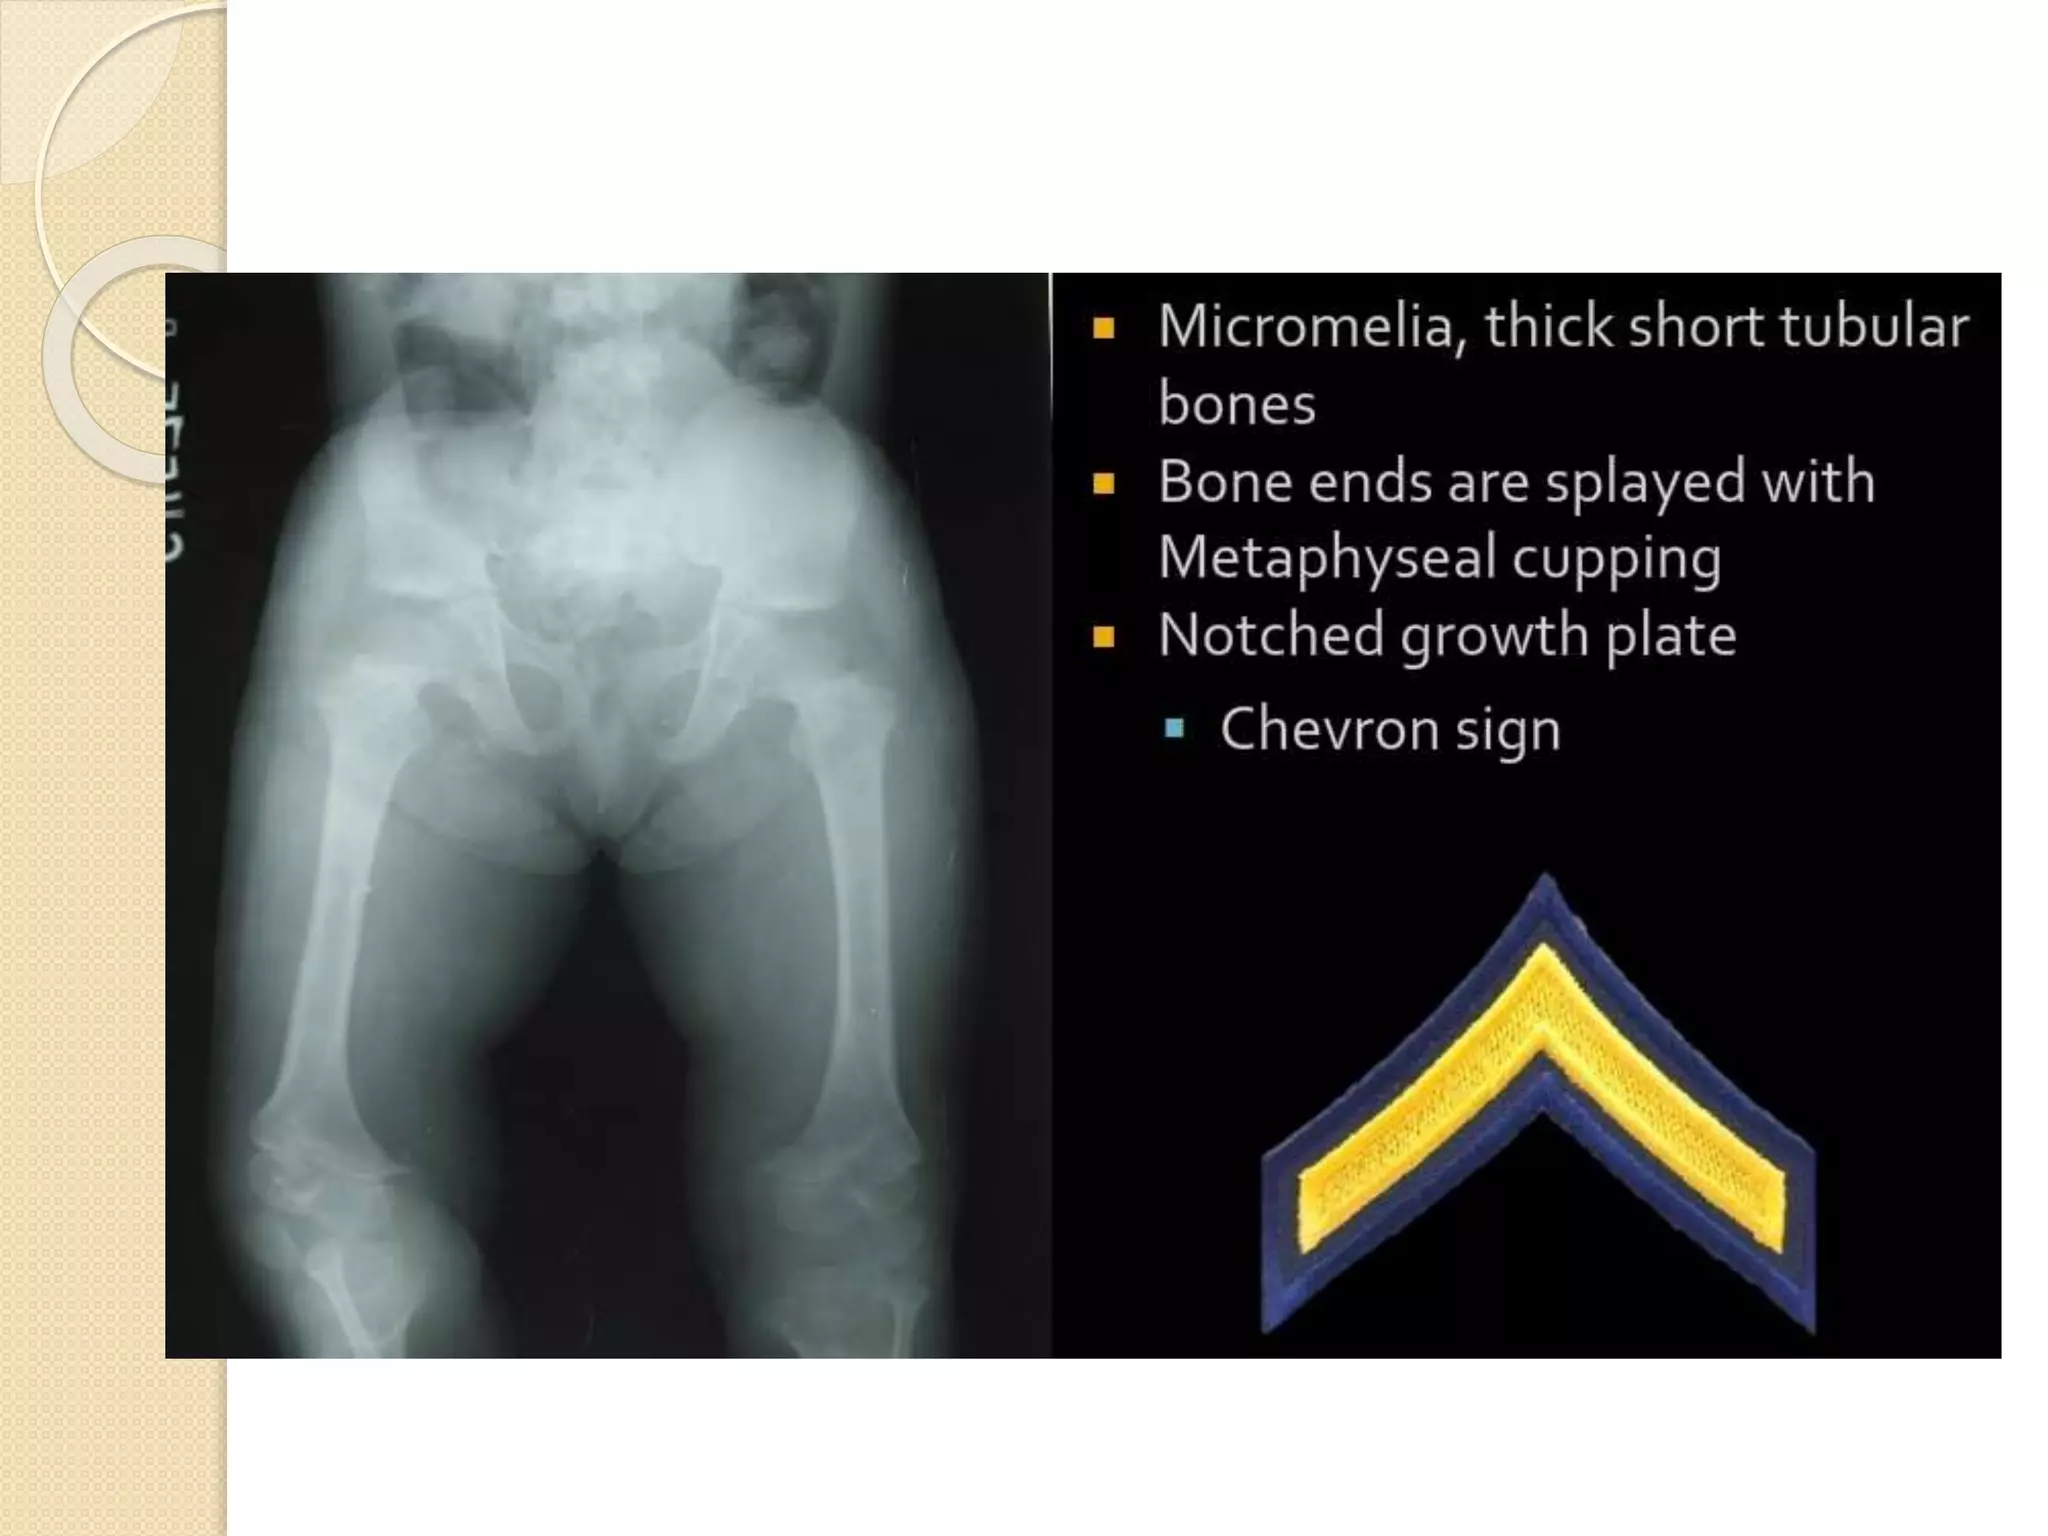

METAPHYSEAL

CHONDRODYSPLASIA

 Heterogeneous group of disorders

characterized by metaphyseal

changes of tubular bones with normal

epiphyses

 Defect in the proliferative and

hypertrophic zones of the physis

 Metaphyseal flaring & irregularity with

widening of physis.

 x ray shows triking bulbous

metaphyseal expansion of long bones